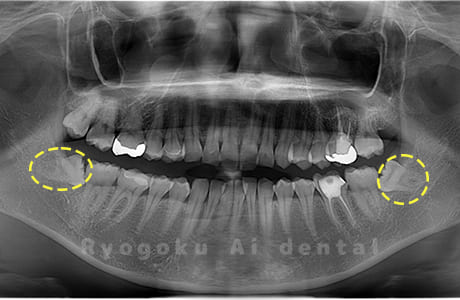

Case01

- 原因

- 水平埋伏智歯

- 治療内容

- 下顎の水平埋伏智歯を抜歯

<リスク・副作用>

手術後は痛み、腫れ、痺れなどの副作用が生じる場合があります。